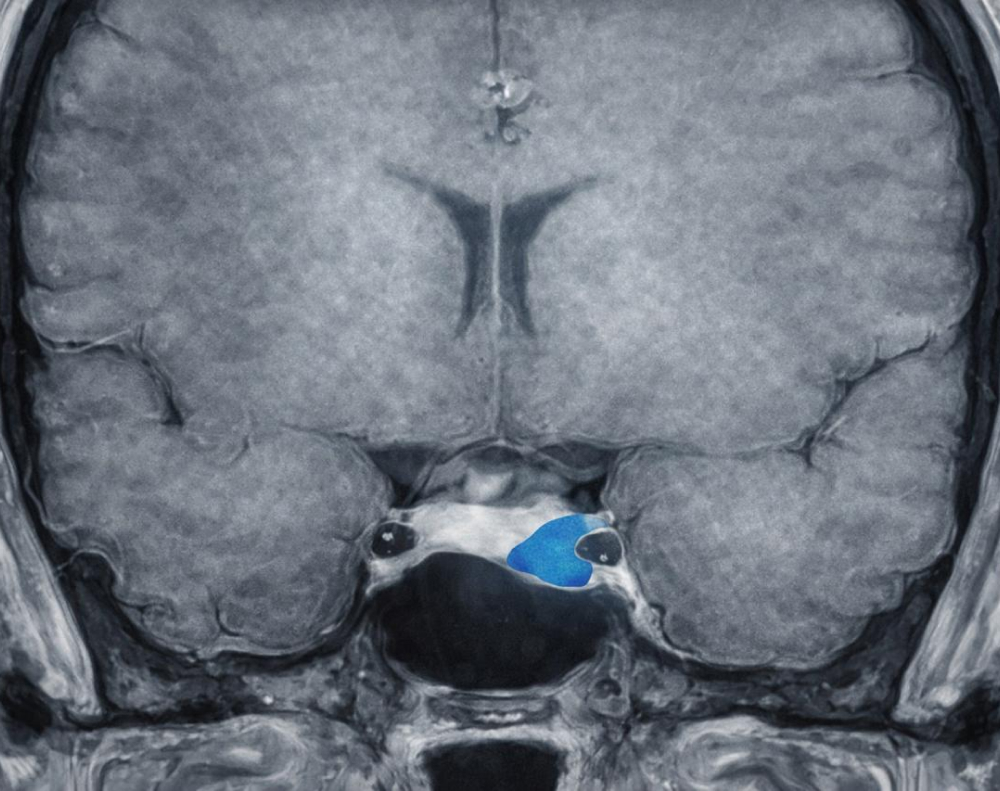

• Imágenes. Resonancia magnética para localizar el tumor en la hipófisis y evaluar su tamaño.